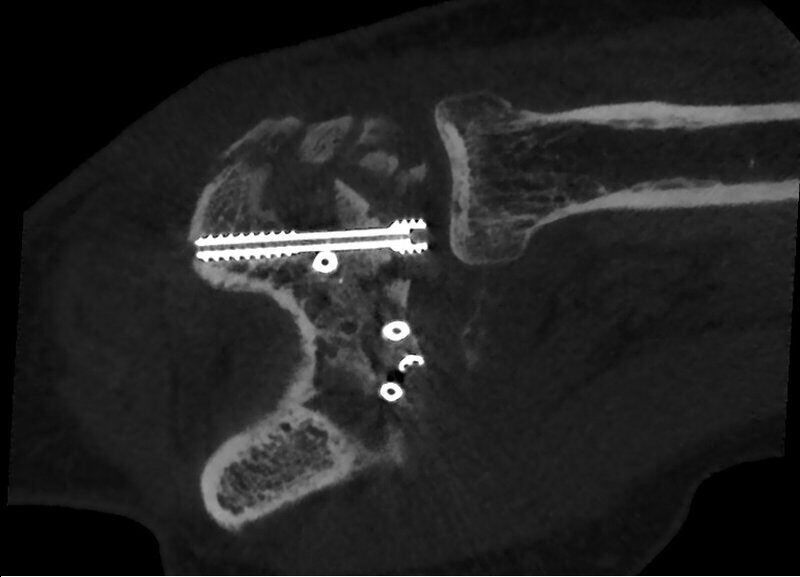

- Fractura de capítulo y tróclea con medio de osteosíntesis

Fractura de escafoides con material de osteosíntesis.